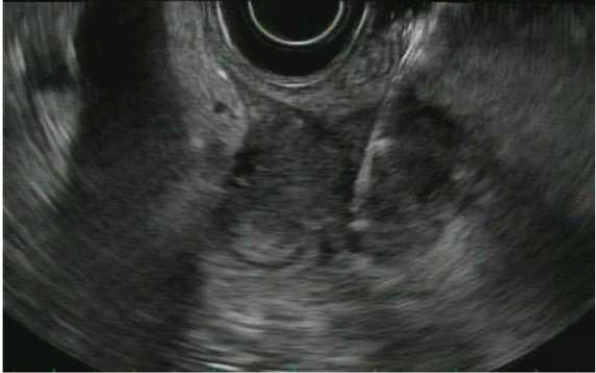

Endoscopic Ultrasonography (EUS) with fine needle aspiration

Endoscopic Ultrasound with Fine Needle Aspiration is a minimally invasive procedure that can be used to obtain tissue samples from lesions around the gastrointestinal tract to aid in diagnosis. It involves advancing a special endoscope into the stomach or small intestine, and using ultrasound from inside the gastrointestinal lumen to visualize the deep layers of the gastrointestinal walls as well as structures nearby to the lumen including the pancreas, the liver, and lymph nodes. Once visualized, a needle can be advanced from the scope into the desired lesion under direct visualization to obtain cells to be examined under a microscope.